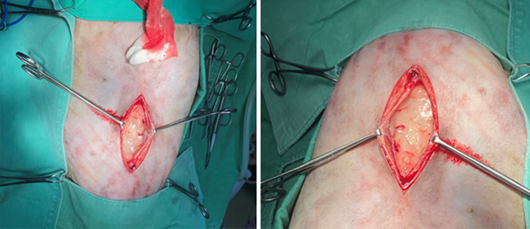

膽囊黏液囊腫』的紅貴賓犬,即時就診,決定動手術切除膽囊。

罹患『膽囊黏液囊腫』的貴賓犬!因行為異常而被帶到『啄木鳥動物醫院』就診。在血檢時發現肝膽指數偏高,做腹部超音波時,又發現肝腫大,膽囊黏性囊腫的情形,很可能是膽道阻塞引起的肝腫大及膽囊腫大。另外 Mini 的膽囊膽沙淤積阻塞現象,在超音波底下無所遁形,經過膽囊摘除手術,術後兩天就能正常吃喝了,但只要多拖延1~2天,一旦膽囊破裂就會有生命的危險。

早期治療從內科的口服藥開始,最好搭配外科超音波定期追蹤,如果口服藥治療無效,要趕快動外科手術、進行膽囊摘除。因為黏性囊腫阻塞,很容易導致死亡,從膽管阻塞到膽囊破裂,可能拖延很久,一旦膽囊破裂,極具刺激性的膽汁、溢入腹腔(膽汁型腹膜炎)2~3天就可能死亡!因此大部份『膽囊黏液囊腫』都會用到外科,只要即時切除膽囊,狗狗的生命就算保住了。